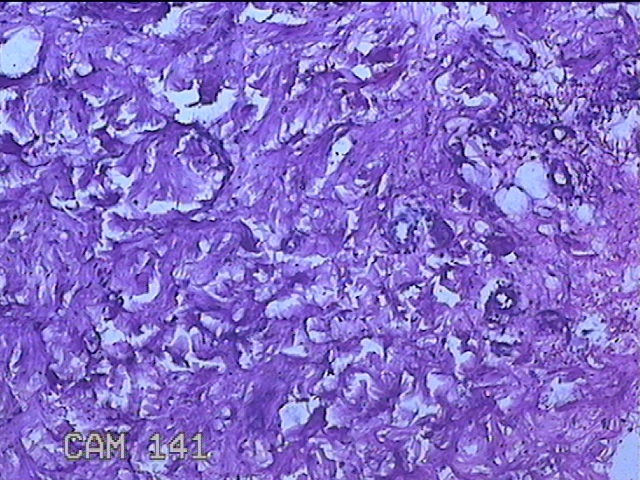

左侧臀部结节

性别

男

年龄

40岁

临床诊断

皮下结节

一般病史

发现左侧臀部结节1年余。

标本名称

大体所见

灰白粉红色组织1.3x0.8x0.3cm一块,表面带梭形皮肤1.3x0.8cm,皮下见结节1.3x1x0.7cm一个,切开结节呈实性,切面灰白粉红色,质软。

图1